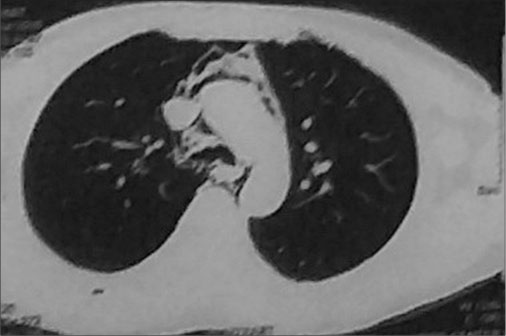

Two months after treatment completion (second follow-up), the patient presented with breathlessness. Chest X-ray (posteroanterior view) [Figure 1] and CT of the neck and chest showed extensive subcutaneous emphysema in the neck and axilla extending to the mediastinum [Figure 2]. He was referred to the chest unit where an intercostal drain (ICD) was inserted. The ICD relieved the pneumomediastinum and subcutaneous emphysema, and the patient was symptomatically better. After withdrawing the ICD, he was discharged from hospital. One week later, he died suddenly at home after an attack of coughing.

| Figure.2:Computed tomography of the neck and chest showed extensive subcutaneous emphysema in the neck and axilla extending to the mediastinum

A chest X-ray usually detects pneumomediastinum and subcutaneous emphysema although better visualization is obtained through CT scan. In our case, CT scan showed extensive pneumomediastinum and subcutaneous emphysema. The patient underwent respiratory failure, which resulted in his death 2 months after the completion of treatment. The respiratory failure may have been chemotherapy drug induced or caused by forced expiration (e.g., the Valsalva maneuver with breath holding for a prolonged period).[2]